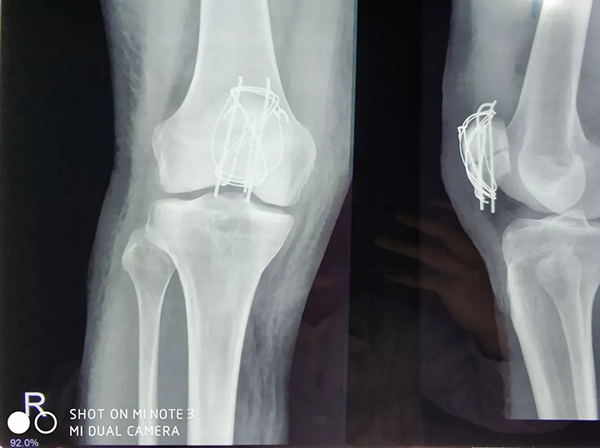

近日,廣安醫(yī)院關(guān)節(jié)科羅軍主任帶領(lǐng)科室團(tuán)隊(duì)成員為一名來自俄羅斯的患者成功施行了右髕骨粉碎性骨折切復(fù)內(nèi)固定手術(shù)治療,術(shù)后三天患者能自行起床活動(dòng)。

患者從遙遠(yuǎn)的俄羅斯來到美麗的舟山群島船廠指導(dǎo)工作,旅途中不慎跌倒,導(dǎo)致右髕骨粉碎性骨折,需行手術(shù)治療,患者來到廣安醫(yī)院就診,然而語言不通,患者只能聽懂簡(jiǎn)單的英文,怎么辦?機(jī)智的易觀俊主治醫(yī)師用手機(jī)上的翻譯軟件,搭好了醫(yī)患溝通的橋梁。